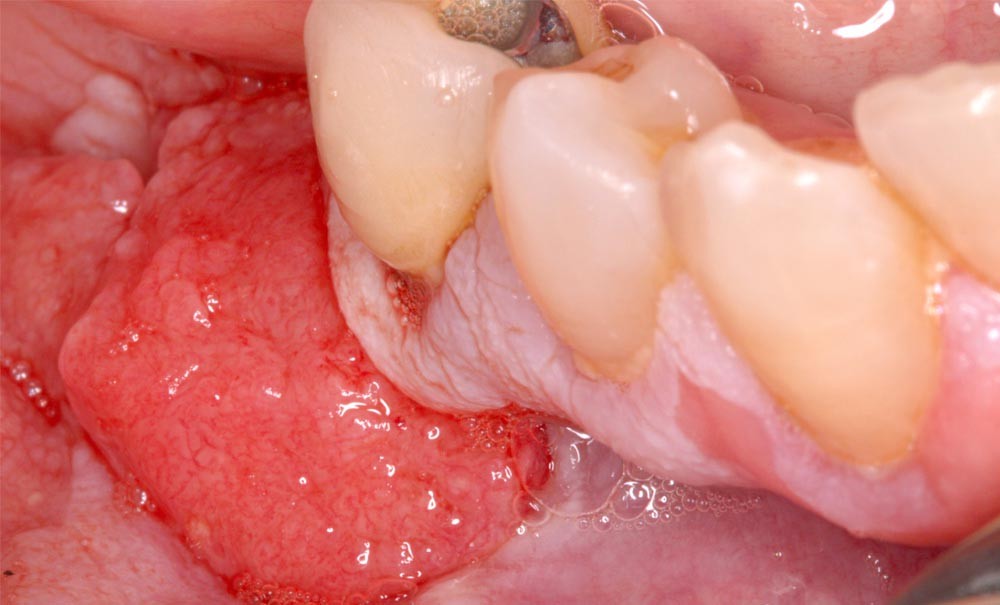

Quel que soit le type d’hépatite, les répercussions s’étendent au-delà du foie. Parmi les manifestations extra-hépatiques, l’atteinte de la cavité buccale est souvent sous-estimée, bien qu’elle puisse avoir un impact significatif sur la qualité de vie des patients. Parmi les complications orales, les plus fréquemment rapportées sont le lichen oral, l’hyposialie, les maladies parodontales ou encore des troubles de l’hémostase. Ces manifestations cliniques peuvent être des signes évocateurs d’une hépatite, notamment lorsque celle-ci évolue sous une forme chronique. La pathogenèse de ces affections repose sur des effets directs du virus sur les tissus buccaux ainsi que sur des effets indirects liés à la réponse immunitaire antivirale.

Article réservé à nos abonnés Les épulis

Quelles sont les 7 formes cliniques des épulis ? 1. Épulis inflammatoire (plasmocytaire) Nodule indolore, pédiculé, érythémateux, parfois ulcéré (fig. 1a)....